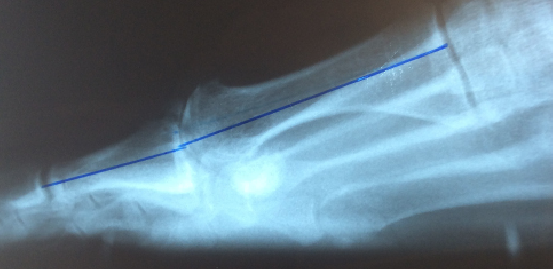

Metatarsu

s primus elevatus is basically a radiographic finding that theoretically depicts the position of the first metatarsal relative to the lesser metatarsals at the midstance phase of the gait cycle.18 In metatarsus primus elevatus, the first metatarsal is elevated to an abnormal position. However, there is no agreement as to the degree that this elevation is truly “abnormal” or pathologic. Some authors have noted that metatarsus primus elevatus can be present in normal, healthy feet with no evidence of hallux rigidus.19

Many authors have connected metatarsus primus elevatus as a causative factor for hallux rigidus. Meyer reviewed radiographs of 120 patients and found that hallux rigidus findings did correlate with the presence of metatarsus primus elevatus.20 Roukis determined the mean first to second metatarsal elevation to be 5.8 mm in a hallux rigidus group, which was higher than in patients with other foot pathologies.21 Bouaicha and coworkers attempted to standardize techniques to measure alignment of the first metatarsal on lateral radiographs and found that elevation of the first metatarsal greater than 5 mm was predictive of hallux rigidus.17

The fact that hallux rigidus and metatarsus primus elevatus seem to go together when looking at lateral radiographs reaffirmed the long held notion that hypermobility and elevation of the first ray must be a primary cause of hallux rigidus. However, two studies have raised the question about whether such a cause-effect relationship really exists. Horton and coworkers studied radiographs of patients with and without hallux rigidus, and found no difference in alignment of the first ray between the two groups.18 In cases of severe hallux rigidus, the metatarsus primus elevatus increased significantly, suggesting to the authors that elevation of the first metatarsal occurs as a result of hallux rigidus and not vice versa.

Bouaicha and coworkers further studied the role of metatarsus primus elevatus and hallux rigidus.17 They observed that some of the conflicting results of previous studies of metatarsus primus elevatus were due to unreliable measurement techniques of radiographs taken of patients with hallux rigidus. Bouaicha and colleagues described a new measurement technique to measure elevation of the first metatarsal relative to the second metatarsal. With this technique, a correlation between metatarsus primus elevatus and hallux rigidus was present, but the authors could not determine the cause-effect relationship.

However, a more interesting finding was reported in the Bouaicha study regarding the position of the hallux relative to the first metatarsal.17 This angular relationship in the sagittal plane, described as the first metatarsal dorsiflexion angle, showed a significant reduction (i.e. plantarflexion) in patients with hallux rigidus. Furthermore, there was a significant correlation with plantarflexion of the hallux and elevation of the first metatarsal in patients with hallux rigidus. The authors speculated that tensioning of the flexor hallucis longus tendon could be responsible for retrograde metatarsus primus elevatus.